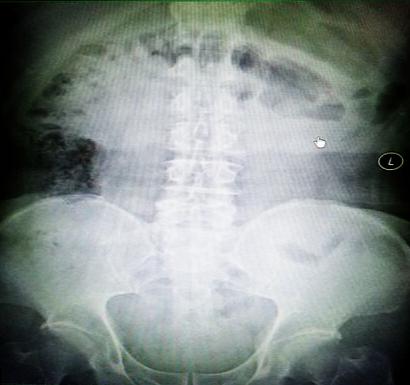

受試患者在結腸端端吻合術中,使用我司新研制產品達到了理想的預期效果。患者術后7天、14X光片顯影,可降解腸道支架均能按研制設計的預期時間節點保持應有強度,術后21X光片顯示可降解腸道支架已完全破碎,并排出體外。在整個試驗過程中,病患無任何不良反映,耐受良好。